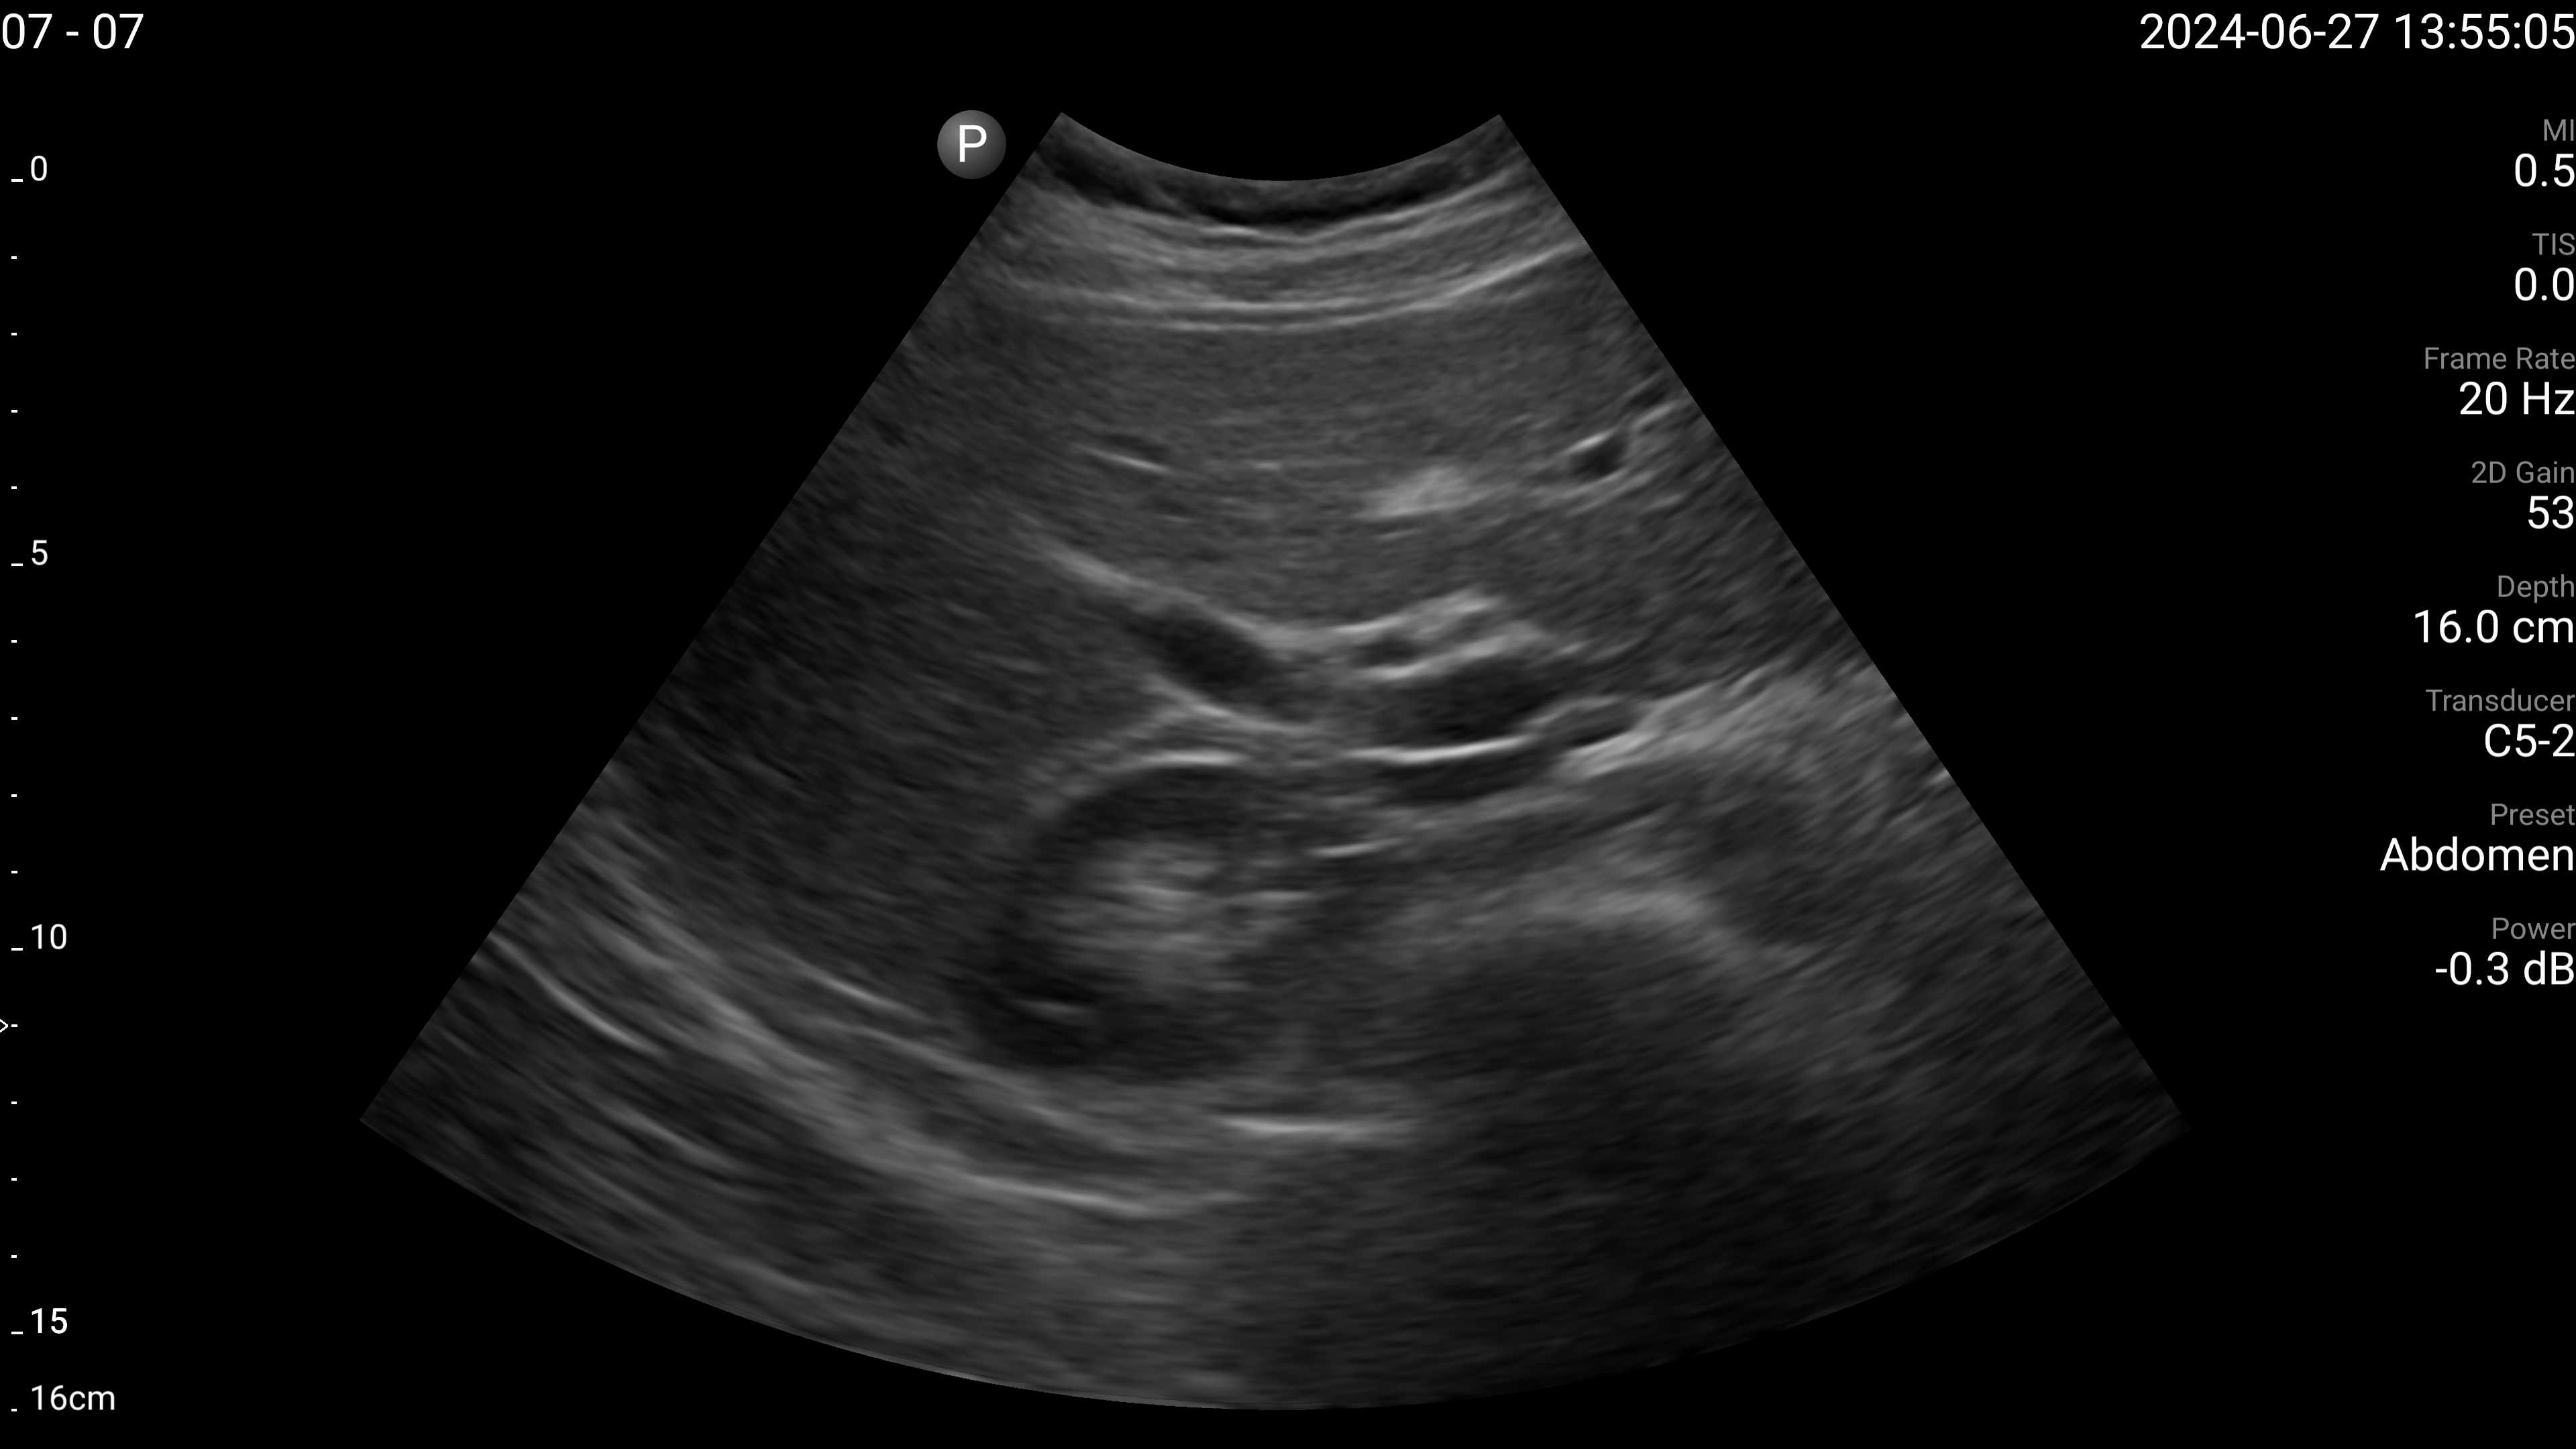

Refer to caption

(a) Proximal aorta with AP diameter.

(b) IVC - longitudinal.

(c) Left lobe of liver - long axis.

(d) Left lobe of liver - transverse.

(e) Right portal vein - transverse.

Figure 4: Examples of the target US images acquired by the sonographers using the human teleoperation system.

The sonographers completed 11 abdominal US scans, each with 5 target images and measurements for a total of 55 images. An example image of each of the targets acquired during these tests is shown in Fig. 4. After completing the scans, two radiologists scored the images based on quality, including identifying targets that could not be seen or were not captured (which were given a score of 0). The distribution of these scores is illustrated in Fig. 5. The first radiologist identified 4 out of the 55 targets as not visible, while the second radiologist identified 6 out of 55 as not visible. Combined, this accounted for 7 unique targets that at least one radiologist considered missing. Of these missing targets, three were not captured due to large amounts of bowel gas and body habitus while one was seen but the sonographer did not capture and save the image. When excluding all the missing targets, the images obtained a mean score of 4.28±0.95plus-or-minus4.280.954.28\pm 0.954.28 ± 0.95 out of 5 and 91.7% of the images were scored 3 or higher by both radiologists. A score of 3 or higher indicated the image quality was sufficient for basic image interpretation. 31.3% of the images were scored 5 by both radiologists, indicating the image quality was good and meaningful image interpretation was easy.